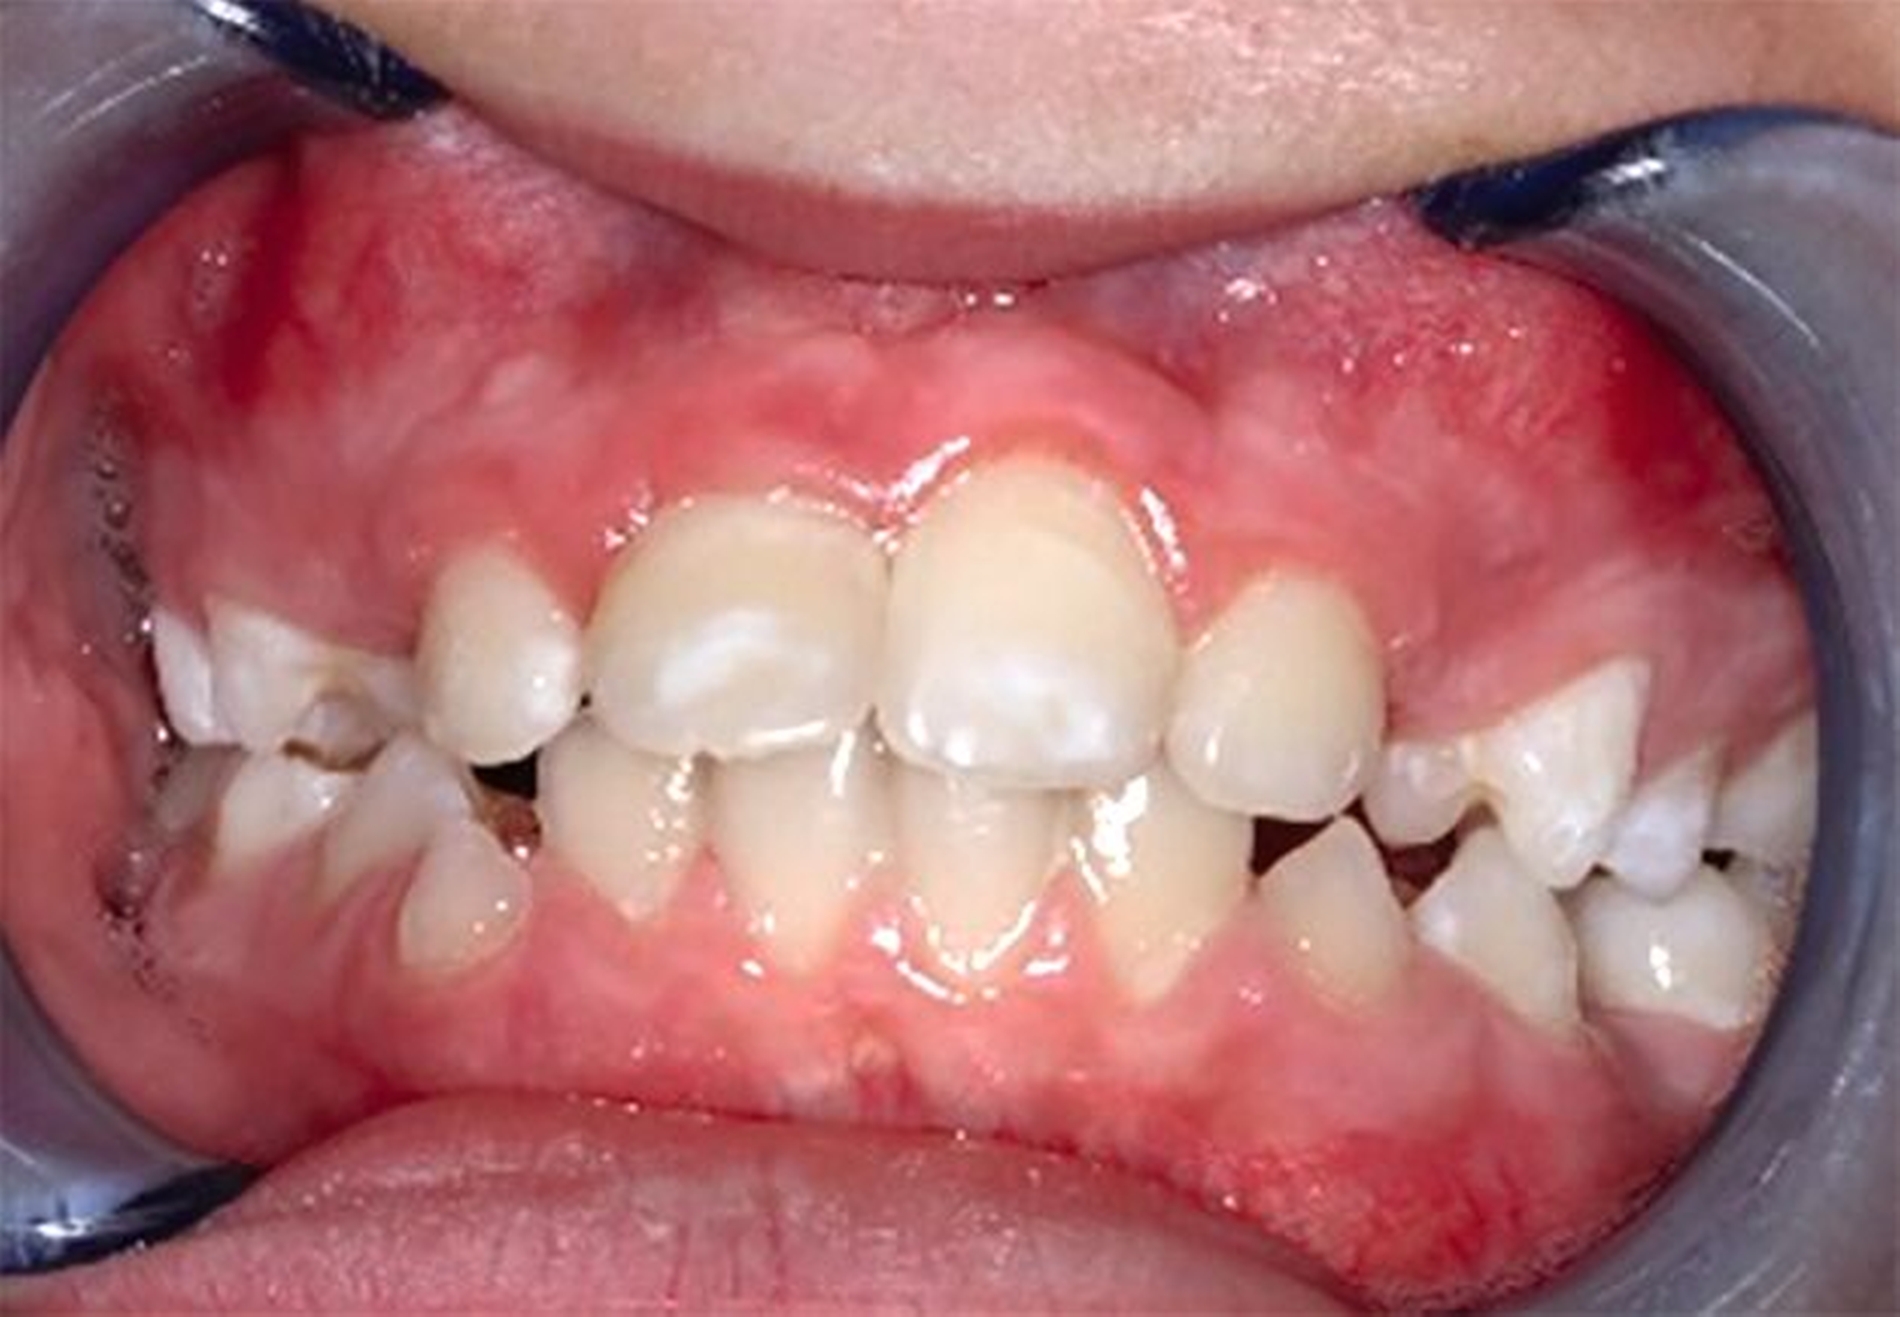

Der ankylosierte Zahn wird schonend gelöst („anluxiert“), bei Bedarf auch osteotomiert und aus seiner ursprünglichen Infraposition und/oder Verlagerung in die Okklusionsposition zum gesunden Nachbarzahn gestellt. Das Ziel dieser Maßnahme ist es, das vertikale Defizit durch die Ankylose-bedingte Wachstumshemmung aufzufangen (Abbildung 3). Je nach dem Zeitpunkt der Maßnahme und dem Verlauf kann der Zahn so vom frühen bis ins späte Wechselgebiss, in günstigen Fällen auch bis ins Erwachsenenalter, erhalten werden. Ob später ein kieferorthopädischer Lückenschluss, eine Prämolaren-Transplantation oder eine Implantation folgt, muss individuell nach der weiteren abzuschätzenden Prognose des Zahnes und nach dem Patientenwunsch entschieden werden.